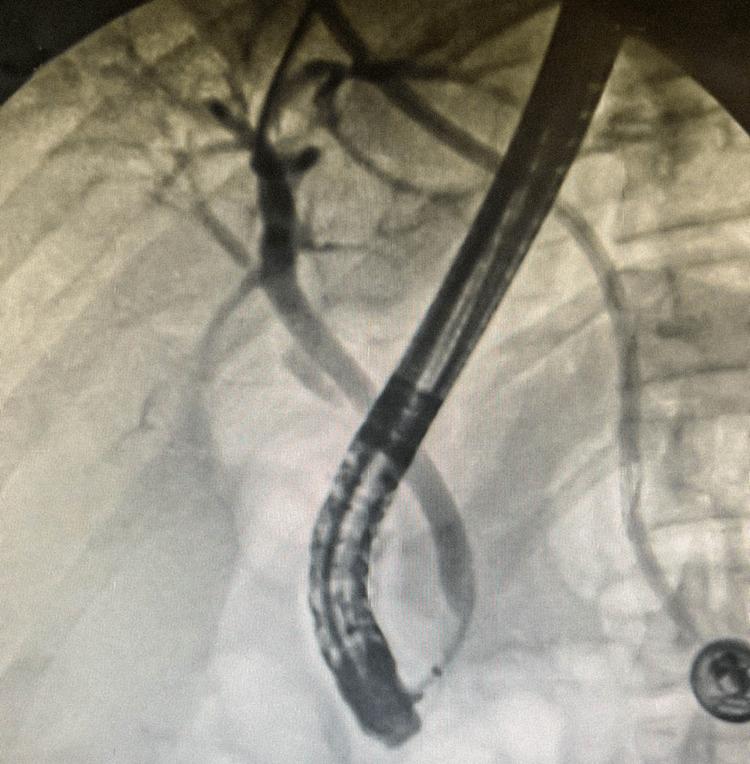

Gallbladder agenesis (GA) is a rare congenital malformation with less than 500 reported cases. Often an incidental finding intraoperatively or in postmortem autopsies, the first reported case dates back to 1701. We discuss the case of a 21-year-old female presenting with classic biliary symptoms who, on imaging, failed to have a visualizable gallbladder. Initial ultrasound (US) reported a non-visualized gallbladder with gallbladder contraction as a possible explanation. More advanced imaging allowed for the preoperative diagnosis, thus preventing an unpleasant intraoperative surprise. As imaging techniques continue to advance, unnecessary operations can hopefully be avoided, albeit a difficult diagnosis to make.

摘要

胆囊缺如(GA)是一种罕见的先天性畸形,报告病例不足500例。通常是在术中或尸检时偶然发现,首例报告病例可追溯到1701年。我们讨论了一名21岁女性的病例,该患者表现出典型的胆道症状,影像学检查未发现可视化胆囊。最初的超声(US)报告胆囊未显示,胆囊收缩可能是一种解释。更先进的影像学检查实现了术前诊断,从而避免了术中令人不快的意外情况。随着成像技术的不断进步,有望避免不必要的手术,尽管这是一个难以做出的诊断。